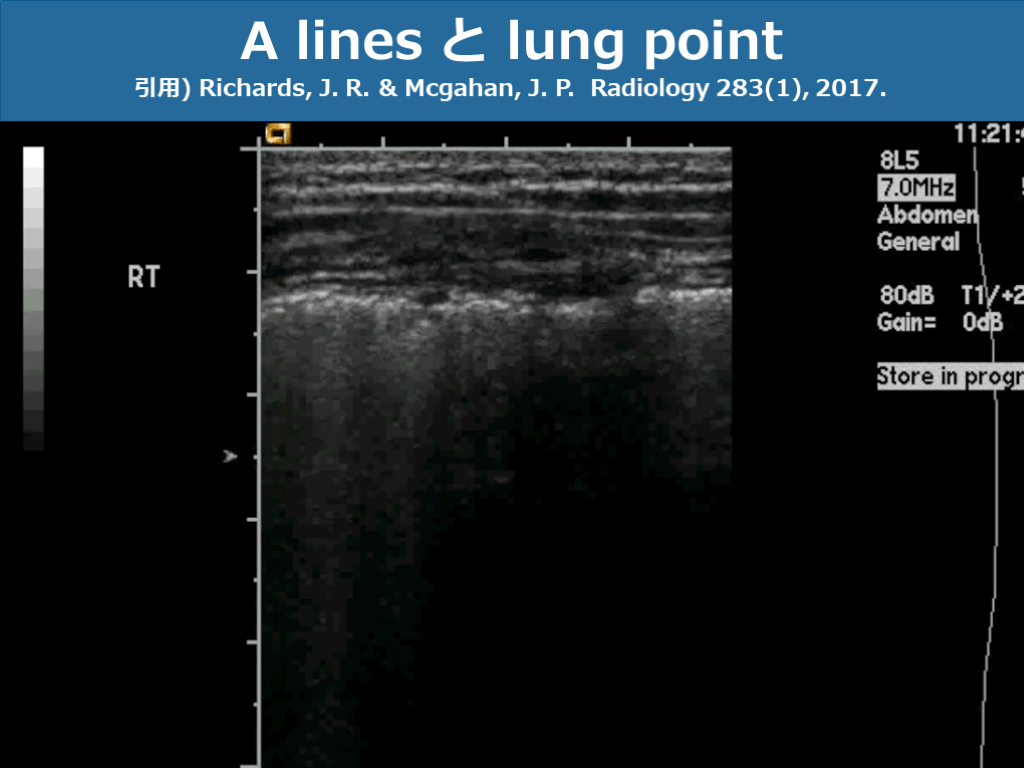

スライド画像)広島大学病院 演者作成 A lines と lung point 引用) Richards, J. R. & Mcgahan, J. P. Radiology 283(1), 2017.

スライド画像)広島大学病院 演者作成 A lines と lung point 引用) Richards, J. R. & Mcgahan, J. P. Radiology 283(1), 2017. A lines Lung point

スライド画像)広島大学病院 演者作成 A lines 引用) Richards, J. R. & Mcgahan, J. P. Radiology 283(1), 2017. ●正常所見 ●水平方向に繰り返し出現  基本的に胸膜とプローベの距離と等間隔に ●プローブの接地面より下は含気のある  正常な肺胞構造  ※気胸でもAlines見られることもあり

スライド画像)広島大学病院 演者作成 Lung point 引用) Richards, J. R. & Mcgahan, J. P. Radiology 283(1), 2017. ●壁側胸膜と臓側胸膜が接している部分と  離れている部分との境界 ●呼吸性に移動 ●気胸に対して高い特異度を示す

スライド画像)広島大学病院 演者作成 Lung point を M mode で比較 引用) Richards, J. R. & Mcgahan, J. P. Radiology 283(1), 2017. seashore sign 正常所見 barcode sign 気胸